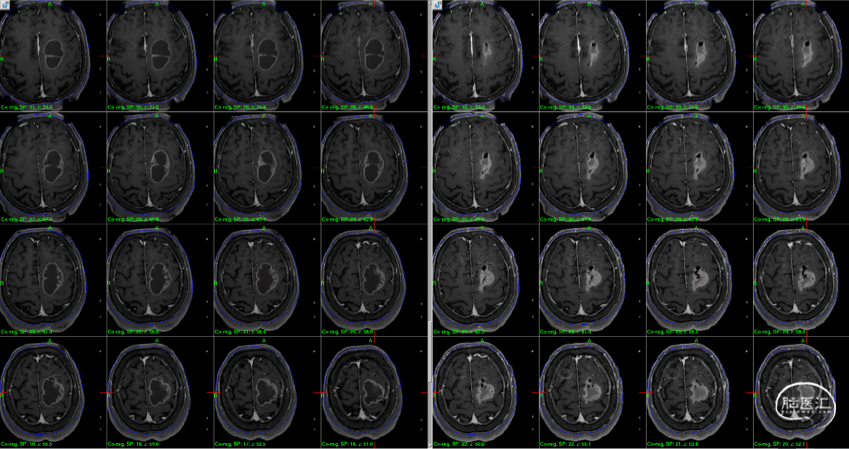

术前影像检查

头颅MRI:显示左额、右侧侧脑室壁占位

1. 较大左侧额上回后部占位,向后挤压中央前回,增强后有明显强化。

2. 右侧侧脑室占位,增强后有明显强化。